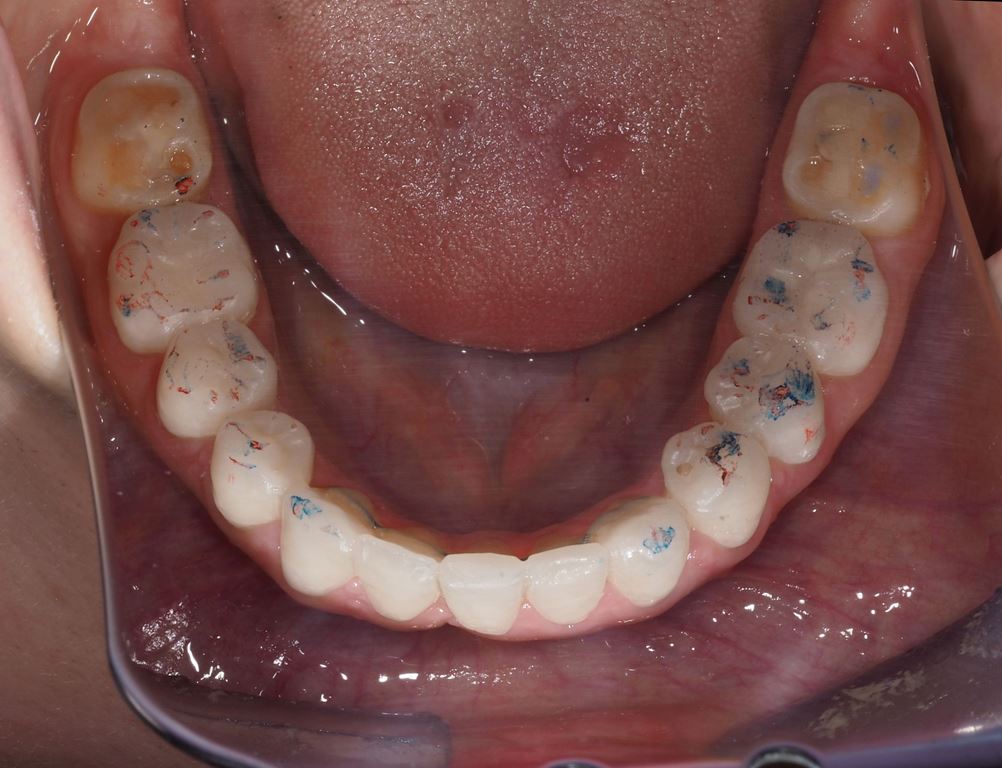

Bezpośrednio po usunięciu zębów rozpoczęto leczenie ortodontyczne, które trwało 15 miesięcy i pozwoliło na uzyskanie zaplanowanych wcześniej pozycji zębów (ryc. 22-24).

Następnie, po okresie stabilizacji i wstępnej korekcie okluzji, na podstawie analizy nowego kompletu zdjęć i modeli, wykonano woskowanie diagnostyczne oraz mock-up górnego łuku zębowego mający na celu potwierdzenie ostatecznego kształtu zębów i zakresu niezbędnego przygotowania chirurgicznego (ryc. 25-27).